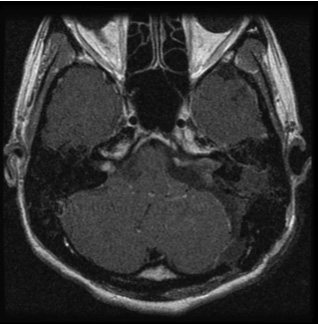

図2:80歳男性 歩行障害をきたした大型神経鞘種

(左図)治療前MRI:顕著な脳の圧迫と脳浮腫を認める

(左図)術後2年後のMRI:薄い残存腫瘍をみとめるが再増大なく、脳の圧迫は改善している

また高齢者でも手術は有益です。図2の症例は80歳の男性症例ですが、10年来右耳難聴で聴神経腫瘍の診断はつけられておりましたが、治療希望せず放置されておりました。しかし歩行障害が進行し当院に紹介されてまいりました。

造影MRIでは大型の腫瘍を認め、周囲の脳幹や小脳が強く圧迫され腫れています。手術にて90%の腫瘍摘出を行い、脳の圧迫もとれ、症状も改善し、治療後3年たった現在でも元気で外来に通っていらっしゃいます。